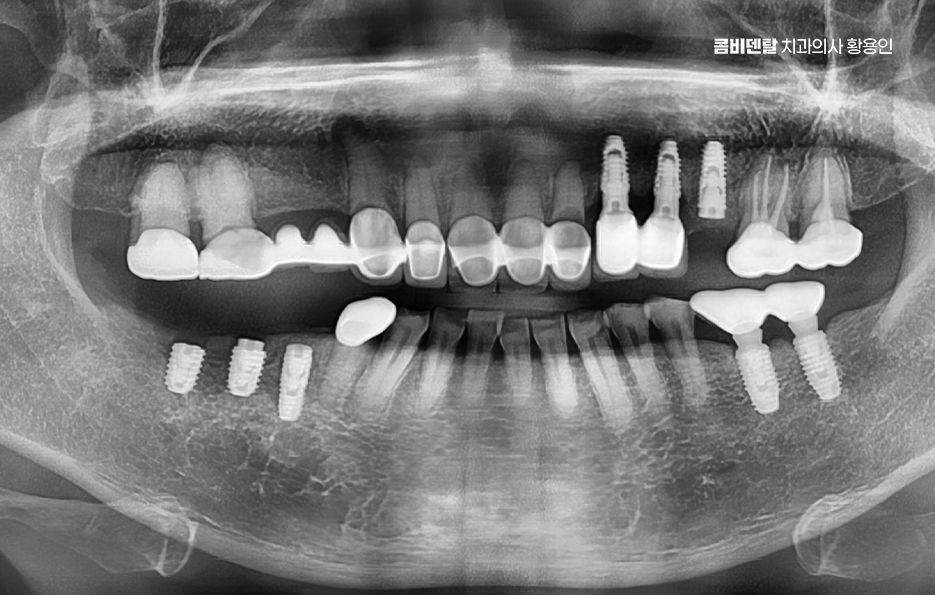

이러한 문제를 막기 위한 효과적인 방법이 바로 임플란트 치료로 어금니 임플란트를 계획할 때는 먼저 잇몸뼈 상태를 정밀하게 확인해야 하며 3D CT 촬영을 통해 뼈의 높이와 두께, 그리고 임플란트를 심을 수 있는 공간을 세밀하게 분석해야 하며 위턱 어금니 같은 경우 상악동이라는 빈 공간이 바로 위에 있어서, 치아가 빠지고 나면 그 공간이 아래로 내려와 임플란트를 심을 자리가 부족해지는 경우가 많고 아래턱 어금니는 하치조신경이라는 중요한 신경이 지나가기 때문에, 신경을 피해서 정확한 위치와 각도로 식립하는 계획이 필요할 수 있어요

결론적으로 어금니 임플란트를 하지 않고 방치하면, 단순히 어금니 하나의 문제가 아니라 전체 교합, 반대편 치아, 나아가 턱관절 기능과 소화 건강까지 영향을 주게 되기 때문에, 가능한 빠르게 치료를 결정하는 것이 장기적으로 더 많은 비용과 시간을 절약하는 방법이 되는 거예요. 특히 뼈가 아직 충분하고, 주변 치아가 건강할 때 임플란트를 진행하면 예후도 좋고, 추가적인 뼈이식이나 부가 수술 없이도 비교적 간단하게 치료가 가능한 경우가 많아서 어금니 상실 후에는 임플란트 치료와의 연계를 잘 고려해서 치료 계획을 늦지 않게 세우시길 바라고 있어요